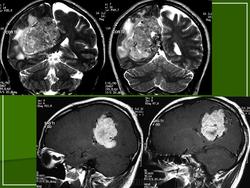

Клинически гемангиоперицитома представляет собой бугристое опухолевидное образование, обычно солитарное, диаметром от 0,5 до 2 см (иногда крупного размера — 35x25 см), различной (мягкой, тестоватой, плотной) консистенции, покрытое неизмененной или синюшно-красной кожей, безболезненное и медленно растущее. Боль (тупая и продолжительная) отмечается при сдавлении опухолью нерва. При определенной локализации опухоли больного могут беспокоить кашель, одышка, тошнота, задержка мочи, гидронефроз, дизурия или запоры; наличием опухоли также могут быть обусловлены телеангиэктазии. одностороннее варикозное расширение вен, геморрой, кровоподтеки, повышение температуры кожи, эндокринные (гипогликемия идр.) и неврологические проявления (при внутричерепных гемангиоперицитомах — головная боль, нарушение походки и равновесия). Опухоль может изъязвляться и давать инфильтрирующий рост, но метастазирует редко.

Макроскопически гемангиоперицитома хорошо отграничена от окружающих тканей или заключена в тонкую капсулу, цвет ее на разрезе варьирует от песочного и серого до розовато-белого, иногда он может быть фиолетовым или красновато-коричневым. Часто встречаются участки некроза, кровоизлияния и явления кистозной дегенерации. При иссечении опухоли нередки профузные кровотечения из окружающего ее большого сплетения крупных сосудов.